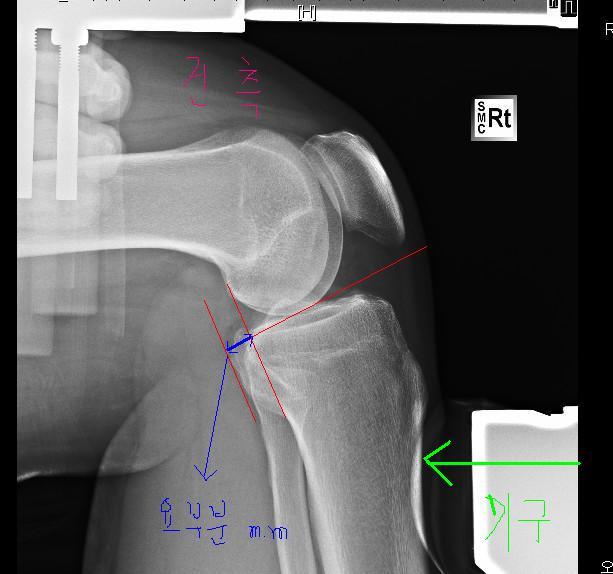

위쪽인 환측(수술한다리) 아래가 건측(안아픈다리)입니다.

자 스트레스뷰<엑스레이>사진을 찍으면 위와 같이 아픈다리 다친다리를 찍습니다. 경골부분을 도구로 밀면서 찍는데요

각 엑스레이사진에서  선을 그어서 파란색선 즉 밀리는 부부을 측정하고  mm수를 의사들이 잽니다.

자 저같은 경우를 살펴봐도 위 사진이 훨씬 더 많이 밀리는게 보이시죠? 이렇게 건측과 환측을 측정해서 동요MM수를 의사들이 보는것입니다.

건측과 환측의 차이입니다. 즉 건측이 4MM , 환측이 12MM이면 동요는 8MM입니다. 12MM가 아닙니다.